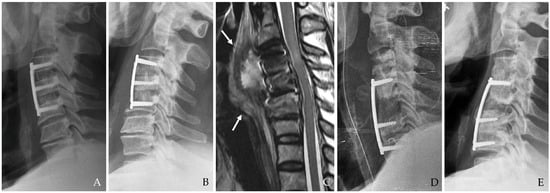

The infection may extend into deeper cervical tissues, forming abscesses that can coalesce and spread into the mediastinum. This is a life-threatening complication characterized by diffuse inflammation, tissue destruction, and multi-organ involvement (Figure 2) [10,12,14]. The time from surgery to abscess formation ranges from several days to weeks, and symptoms may include persistent fever, chest pain, and respiratory compromise.

Figure 2. The patient underwent C5-6-7-T1 anterior cervical discectomy and fusion. At postoperative 6 days, postoperative infection occurred with retropharyngeal abscess and mediastinal extension (white arrows) (AC). Therefore, the patient underwent evacuation of retropharyngeal abscess, irrigation/debridement, removal of plate/screws, and C5-6-7-T1 posterior fixation and achieved a cure for the infection (D).